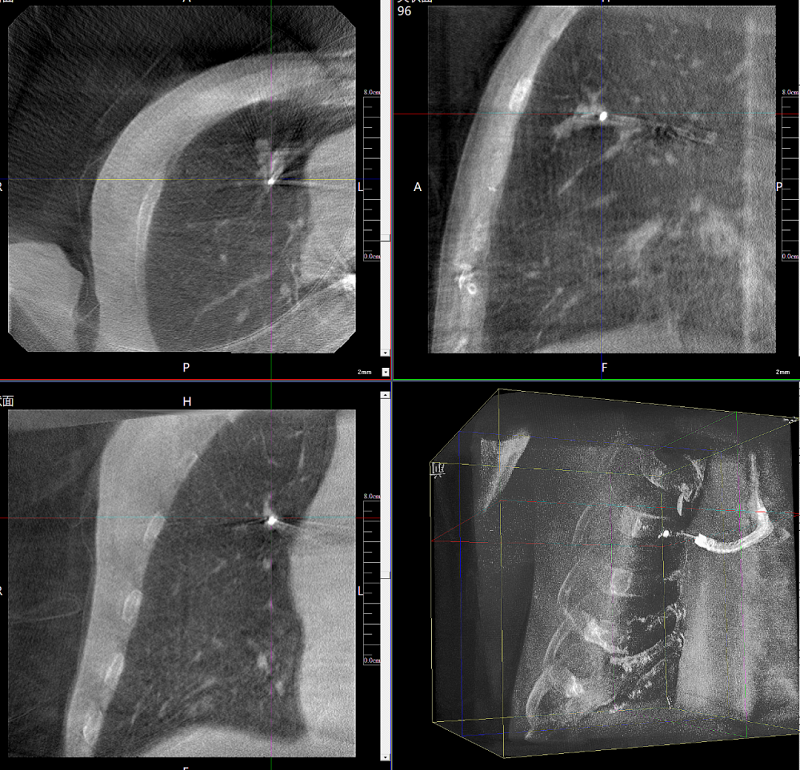

病例3:超聲支氣管鏡下肺活檢(80歲)

三維C形臂還可以創(chuàng)新性地應(yīng)用在呼吸介入領(lǐng)域。例如,在經(jīng)皮穿刺或經(jīng)支氣管鏡肺結(jié)節(jié)活檢、定位、消融等場景中,用于確認(rèn)工具是否到達病灶、消融范圍是否完全覆蓋病灶等。

二維影像無法準(zhǔn)確判斷工具是否到達病灶

三維各切面影像都顯示工具達到病灶內(nèi)

二維C形臂提供的影像存在固有局限性,其成像原理是基于單一方位的投影,導(dǎo)致深部解剖結(jié)構(gòu)信息缺失,且容易受到骨骼和組織的重疊干擾,使得部分病灶難以清晰顯示,甚至被掩蓋。相比之下,三維C形臂通過三維重建技術(shù),可以獲得類似CT的斷層掃描圖像,從而解決了二維影像的重疊問題。

醫(yī)生能夠利用這些三維圖像,更直觀、更深入地分析病變,進行全方位觀察,例如:精確評估骨折復(fù)位情況、清晰顯示內(nèi)植入物的位置及其與周圍組織的關(guān)系等。尤其在復(fù)雜骨折、脊柱手術(shù)、呼吸介入等臨床場景中,三維C形臂提供的詳細(xì)信息對手術(shù)導(dǎo)航和療效評估至關(guān)重要。